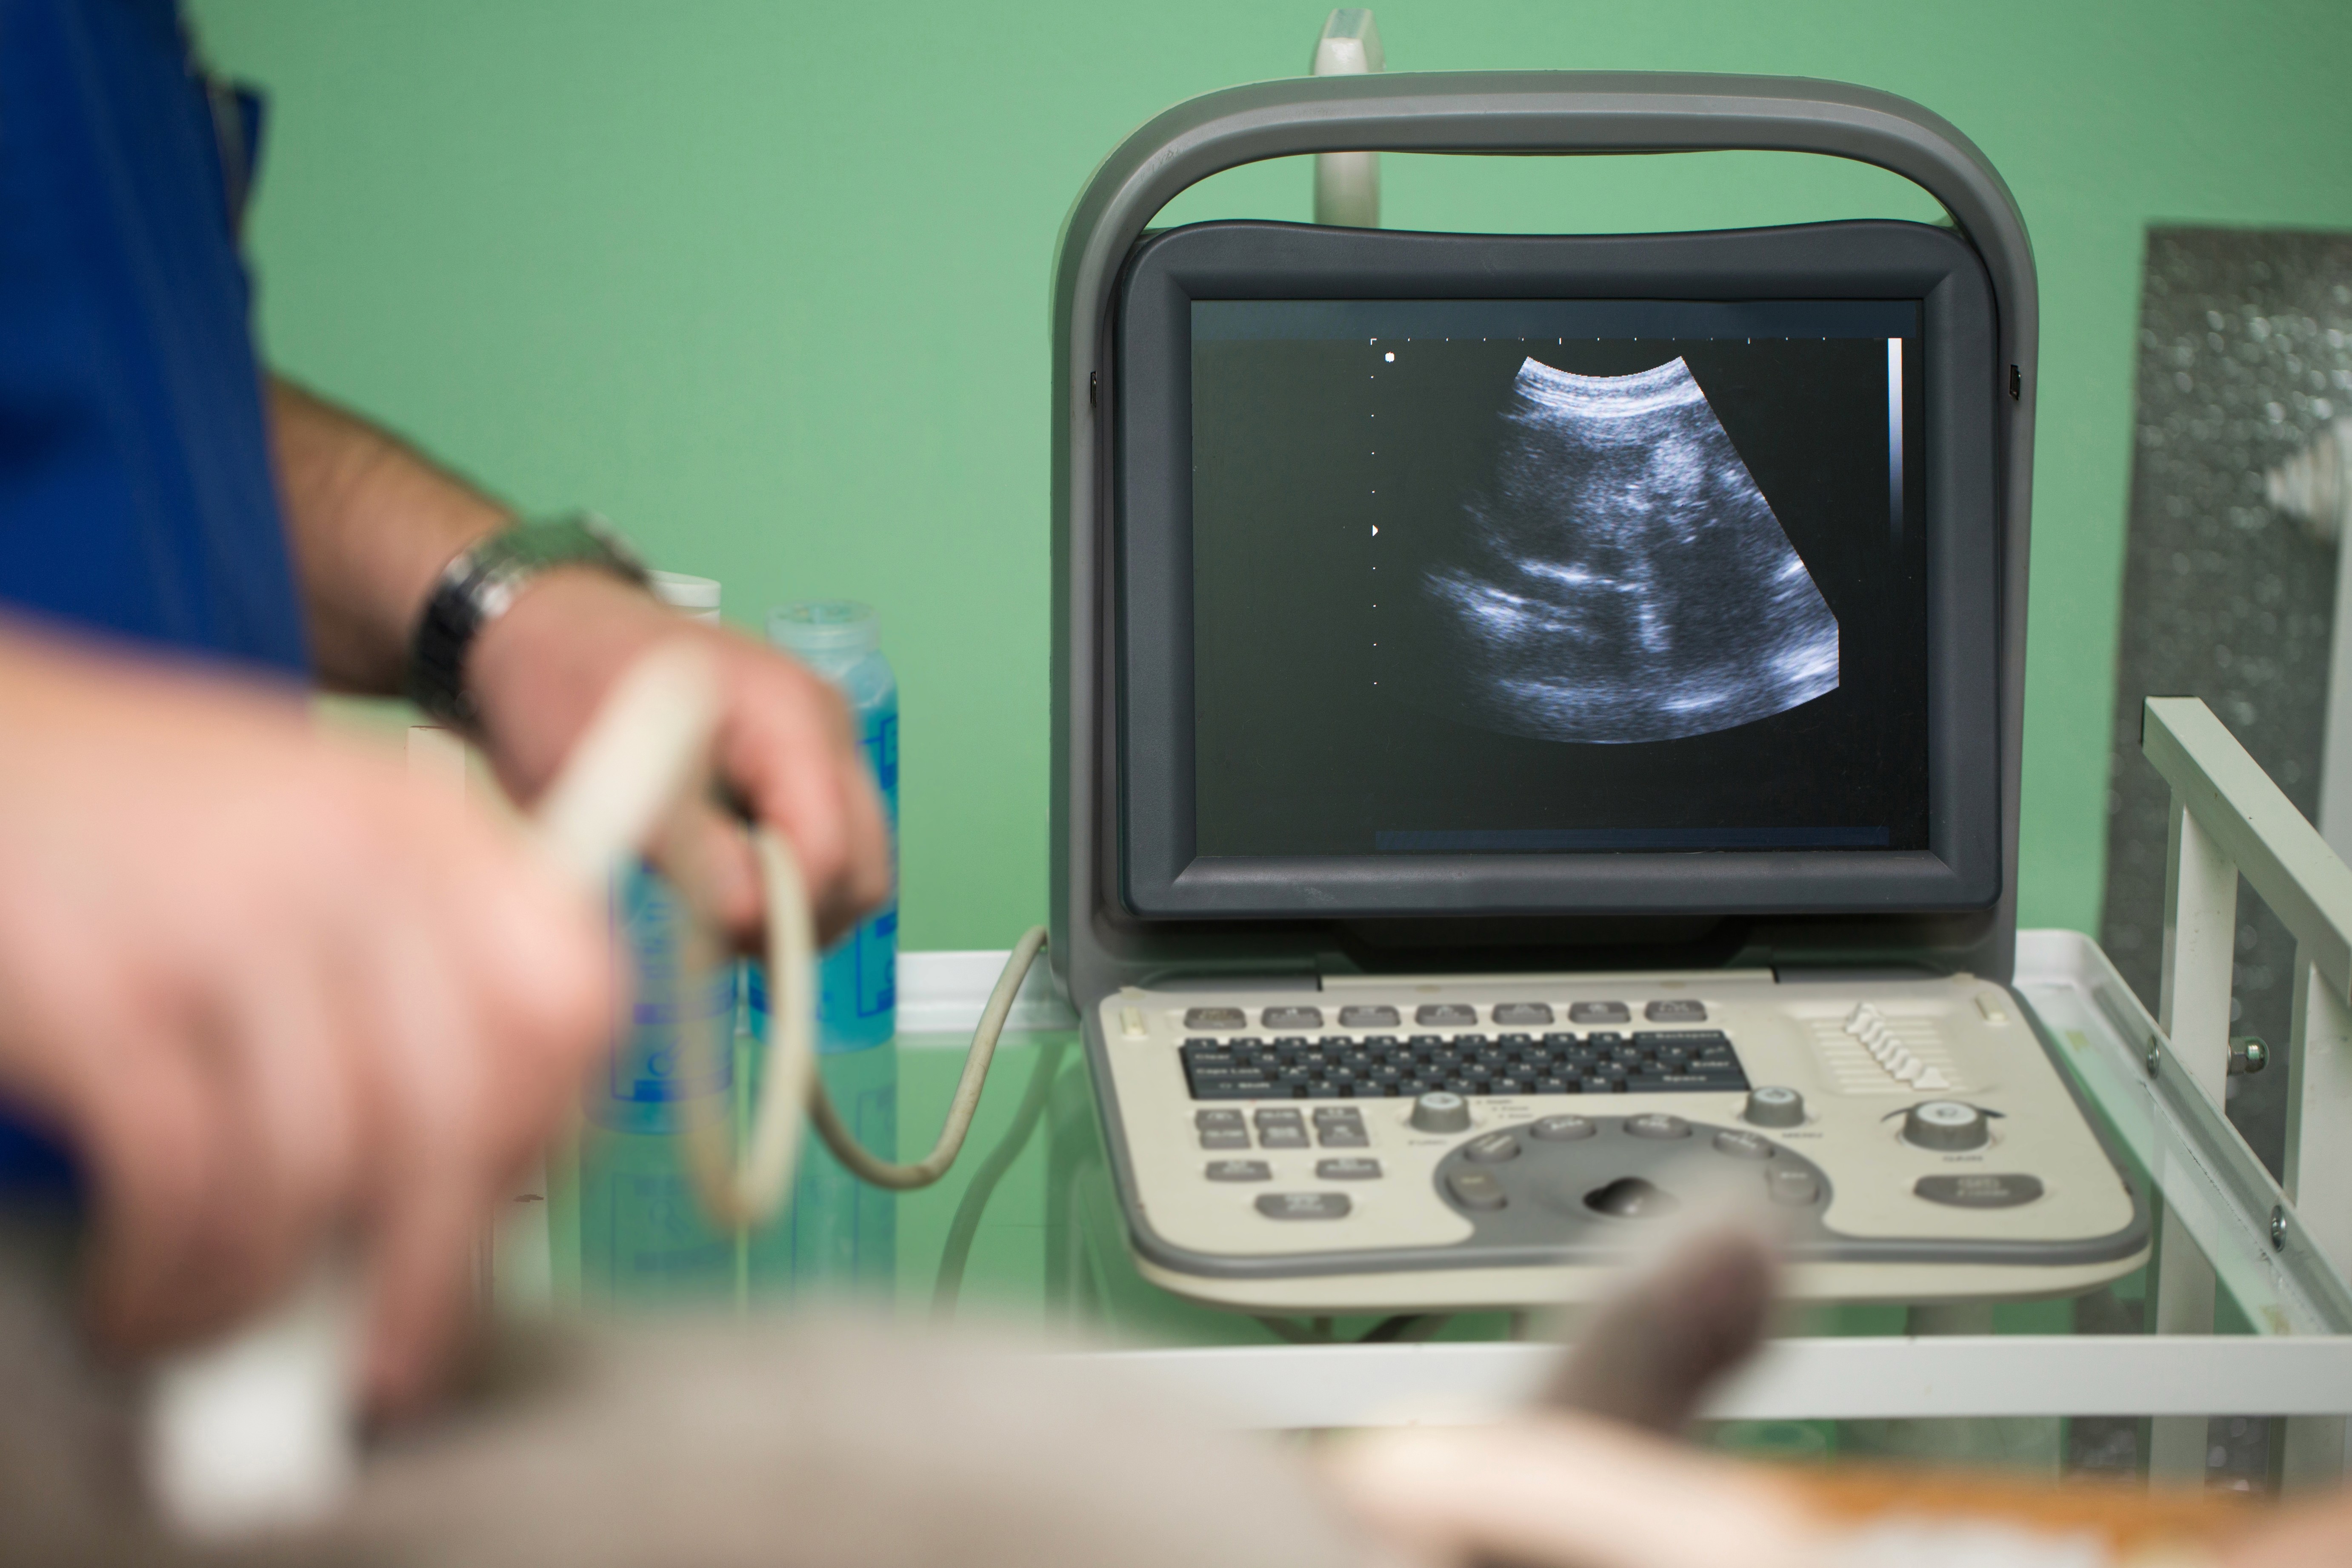

Die Ultraschalluntersuchung (Sonographie) ist ein schmerzfreies, strahlungsfreies Verfahren zur Beurteilung von Weichteilen wie Muskeln, Sehnen, Bändern und Gelenkkapseln. Sie liefert sofortige Ergebnisse und kann direkt in unserer Praxis durchgeführt werden.

Im Gegensatz zum Röntgen, das vor allem Knochen zeigt, macht der Ultraschall Weichteile sichtbar. So können wir Sehnenentzündungen, Muskelverletzungen, Ergüsse und andere Veränderungen schnell und präzise erkennen – ganz ohne Strahlenbelastung.

Die Untersuchung erfolgt in entspannter Atmosphäre. Mit einem Schallkopf und etwas Kontaktgel gleiten wir sanft über die betroffene Körperregion. Die Bilder erscheinen in Echtzeit auf dem Monitor und werden sofort mit Ihnen besprochen.

Die Ergebnisse der Sonographie liegen sofort vor. Wir zeigen Ihnen die Bilder am Bildschirm und erklären genau, was wir sehen. Bei Bedarf können wir direkt im Anschluss gezielte Behandlungen wie Injektionen unter Ultraschallkontrolle durchführen.